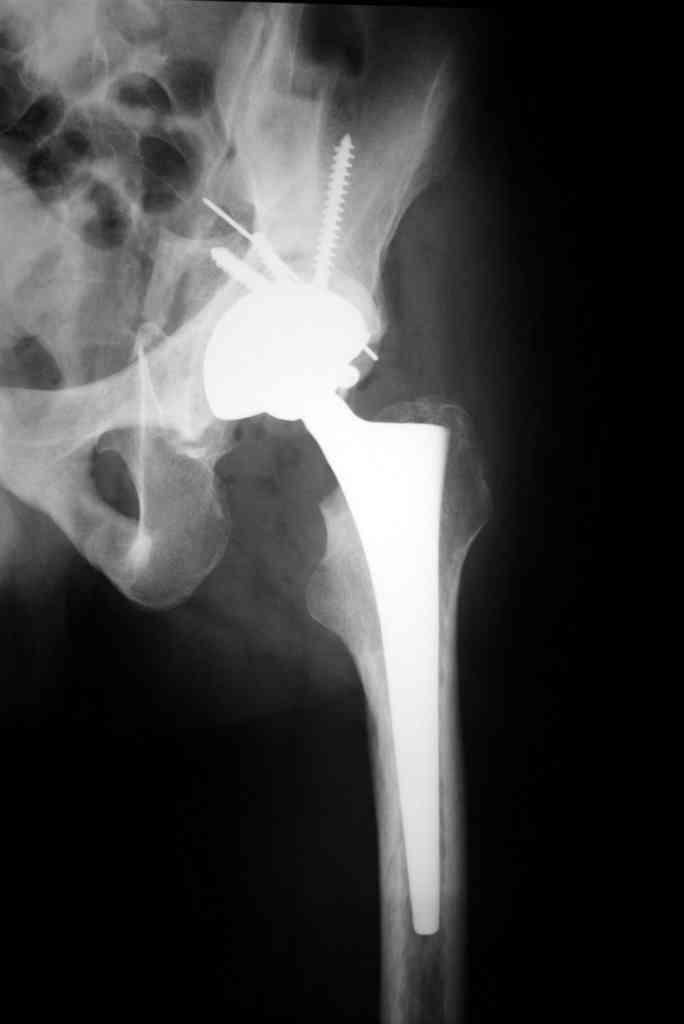

К сожалению, нередкая ситуация, мы предпочитаем выполнять операцию одномоментно - пластика задне-верхнего дефекта крыши ВВ собственной

головкой, установка вертлужного компонента бесцементной фиксации с обязательной дополнительной фиксацией винтами. Проблема будет в

восстановлении длины ноги, опыт показывает, что более 3-х см одномоментно восстановить очень сложно, и даже для этого потребуется широкая мобилизация бедра. В одном из номеров ж-ла Ортопедия травматология России мы опубликовали наш подход и р-ты лечения у больных с последствиями перелома ВВ.

Прилагаю в качестве иллюстрации одну из последних операций.

С уважением, Р.Тихилов